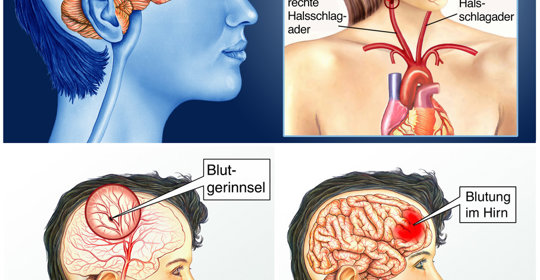

單發性腦梗塞癡呆:症狀、病因、診斷、治療、預後

單發腦梗塞性癡呆:症狀、病因、診斷、治療、預後

大腦大靜脈畸形:症狀、病因、看醫生、檢查、治療

大腦麻木:症狀、病因、就診、檢查、治療

大腦大靜脈擴張:症狀、病因、治療、檢查、看醫生